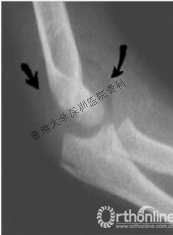

有些隐匿性骨折,仅能从侧位片发现肱骨远端软组织肿胀影,也称八字征。

查体可见肘部肿胀,畸形、压痛和活动受限,x片可见肱骨远端骨折线,有些隐匿性骨折,仅能从侧位片发现肱骨远端软组织肿胀影,也称八字征。有时可同时存在尺桡骨的合并损伤,需加以警惕。